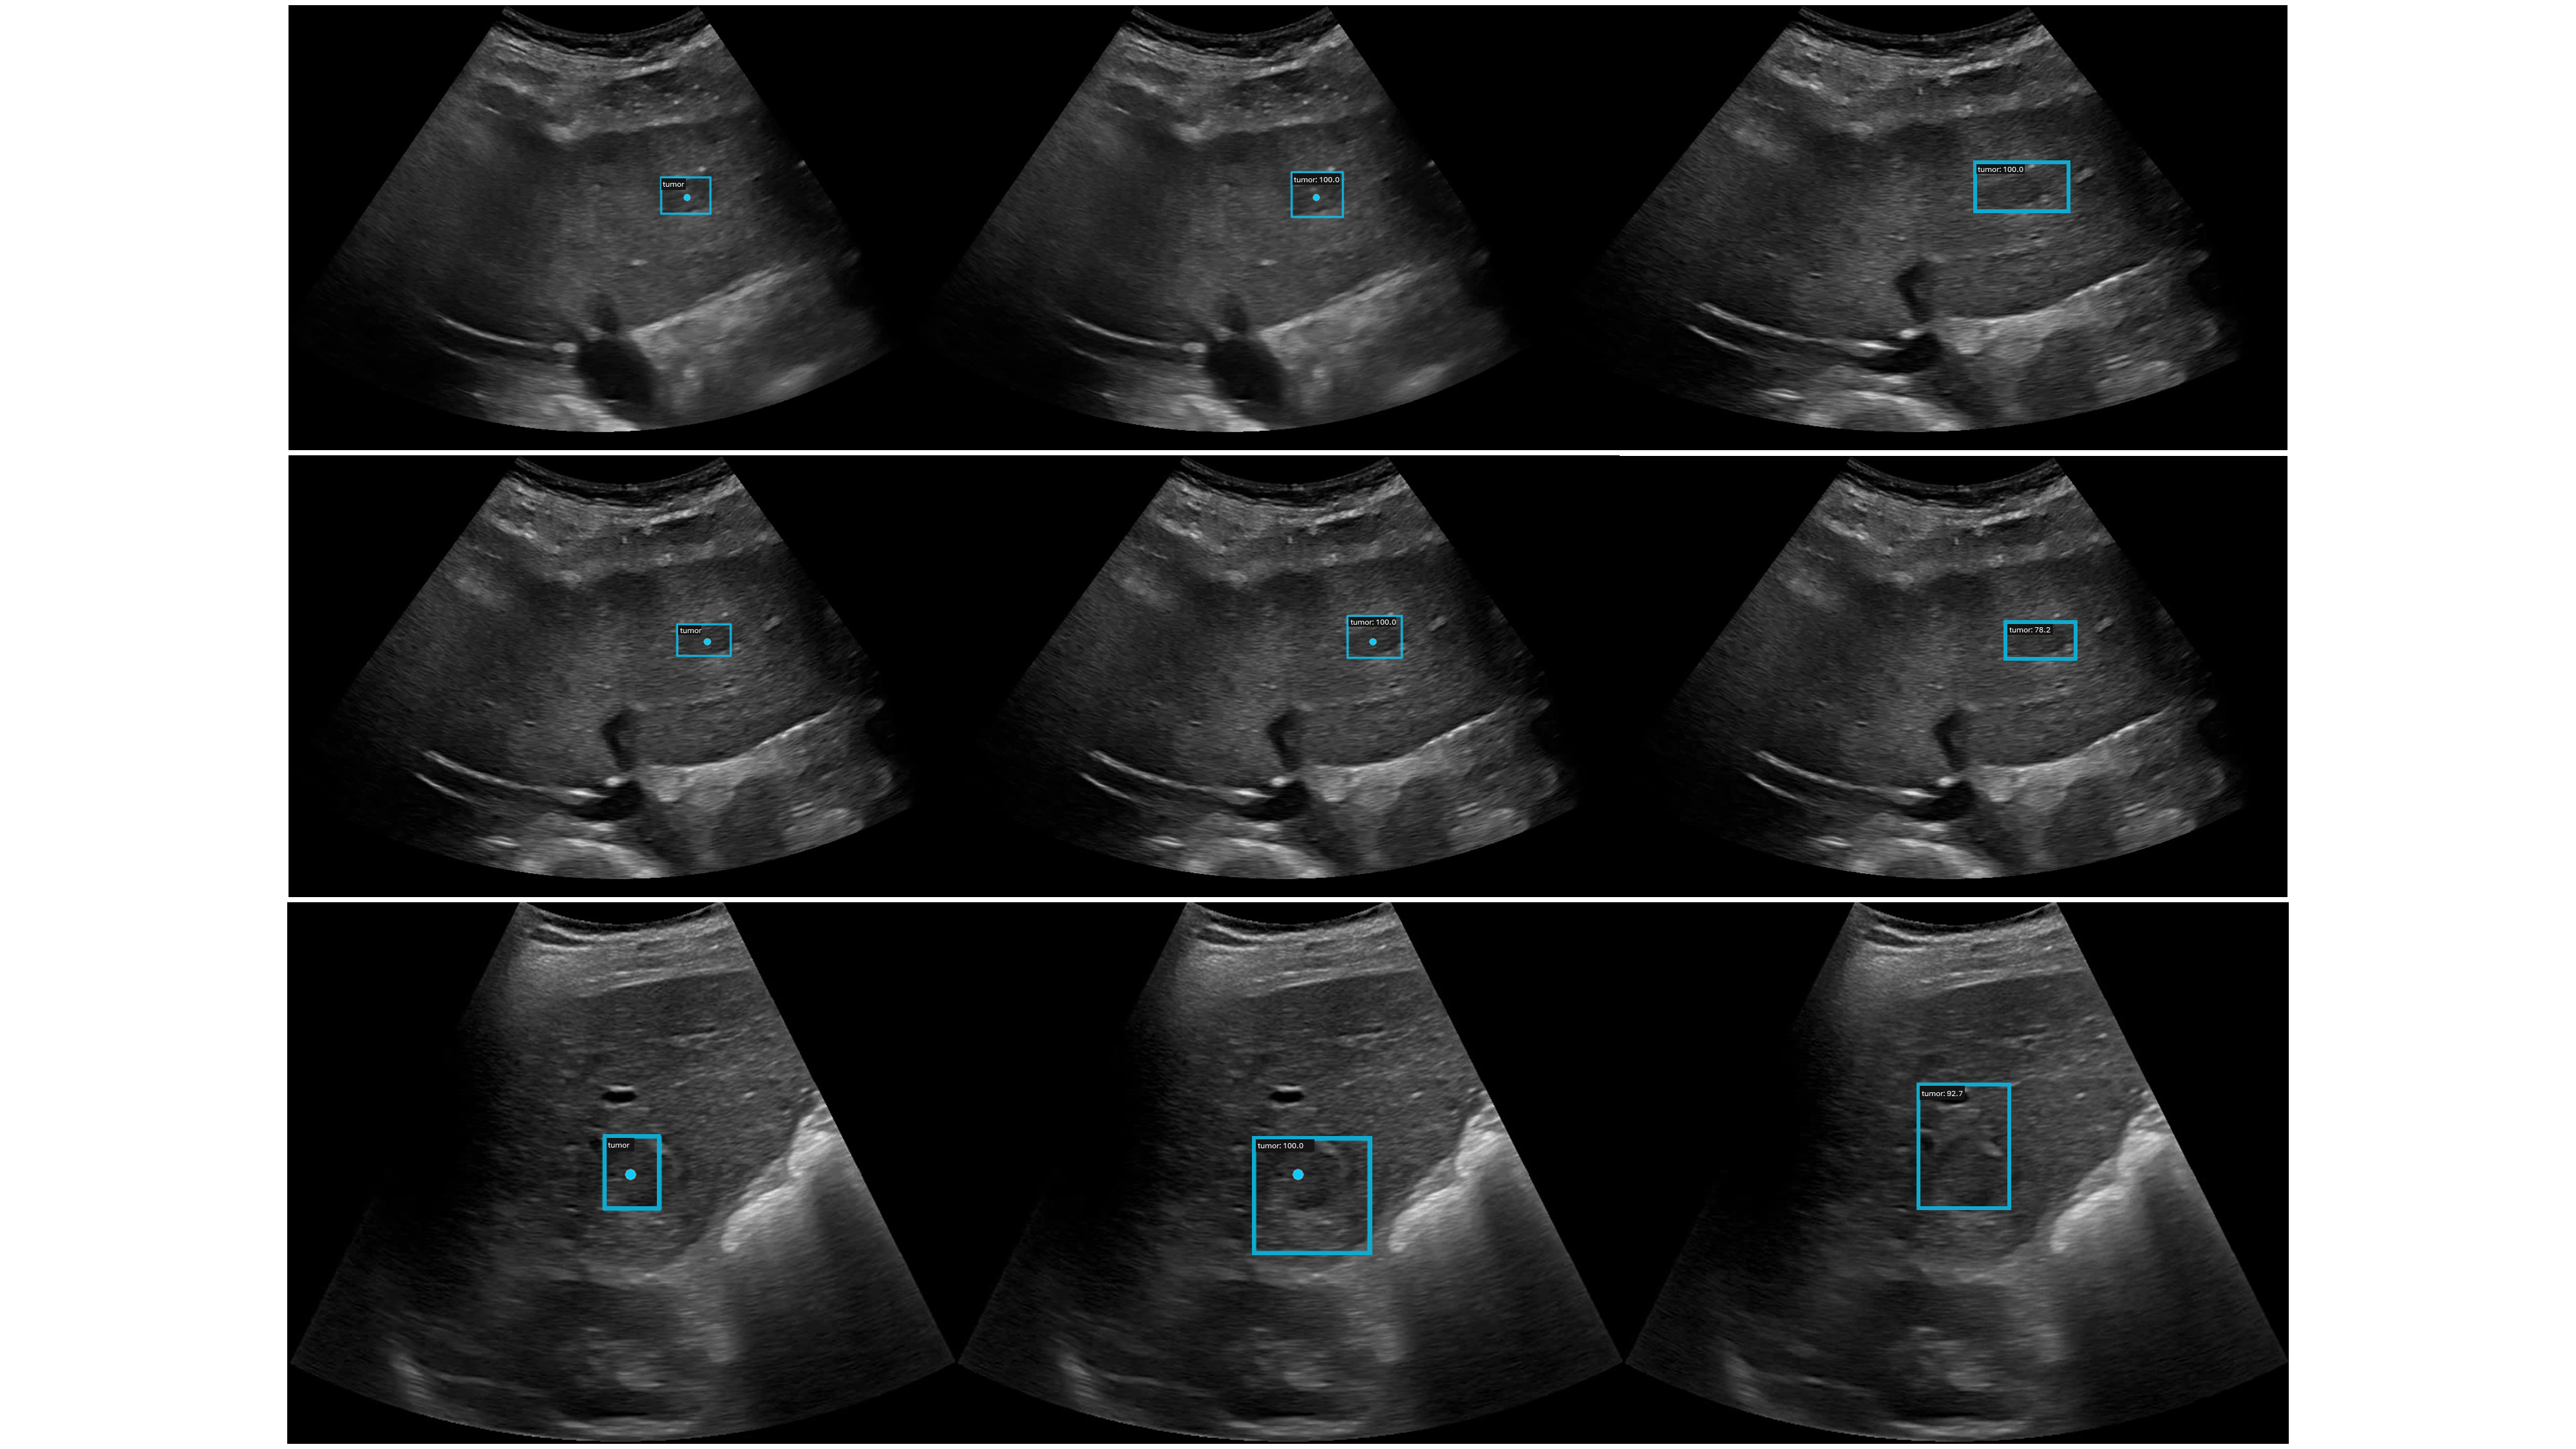

In Fig.5, we showcase qualitative results of our study. The left column displays the ground truth, featuring both point and corresponding bounding box annotations for lesions. The middle column depicts the predicted pseudo-labels with SOTFsubscript𝑆𝑂𝑇𝐹S_{OTF}. The right column displays predictions from the fully-supervised model. The first two rows display instances where accurate pseudo-labels were generated. However, the last row reveals a case where the model failed, incorrectly interpreting the ultrasound artifact, known as acoustic shadowing, as the periphery of the lesion. As mentioned, the OTF point is consistently localized on the near-center of the lesions.

Refer to caption

Fig. 5: Qualitative results of SOTFsubscript𝑆𝑂𝑇𝐹S_{OTF} are presented. The left column displays the ground truth, featuring both point and corresponding bounding box annotations for lesions. The middle column depicts the predicted pseudo-labels with SOTFsubscript𝑆𝑂𝑇𝐹S_{OTF}, and the right column the prediction from the fully supervised model.